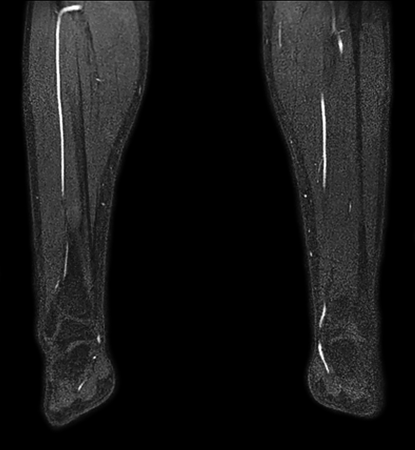

Non-subtraction MR Angiography

Utrecht Medical Center, The Netherlands